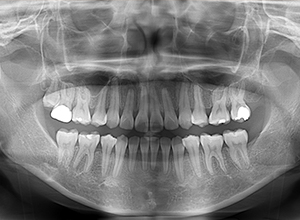

動的治療終了時

X-Ray

批評・予后 治療後、緊密な咬合の確立と共に大幅な切歯の後退によって主訴である口元の突出感と口唇閉鎖不全の改善が得られた。